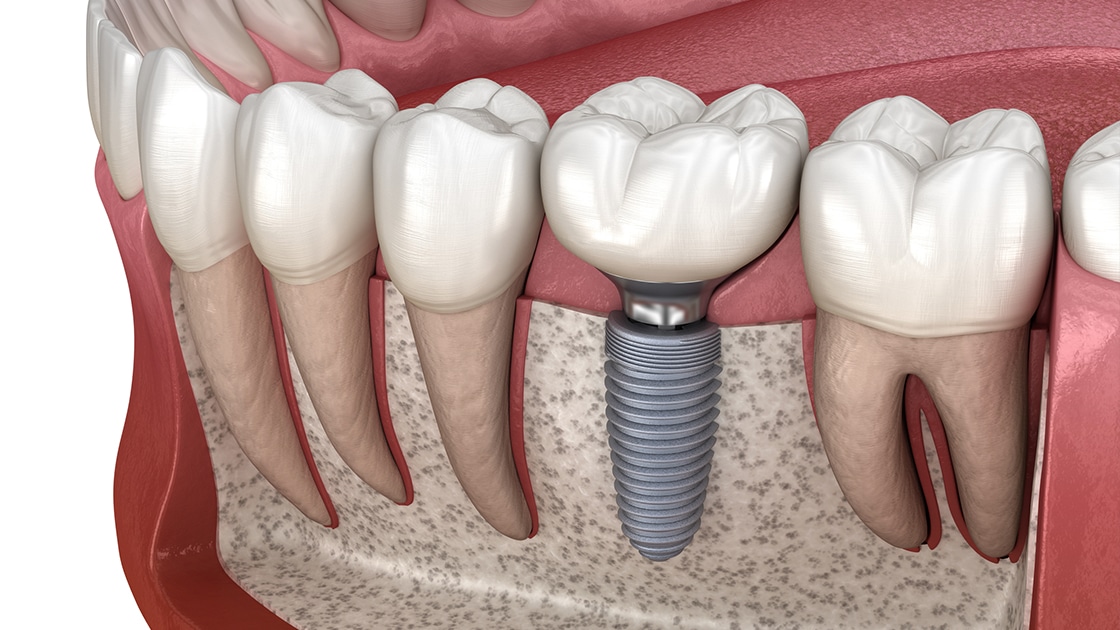

Зубные имплантаты — одна из самых востребованных хирургических процедур в стоматологии. Врач заменяет отсутствующие зубы имплантатами, которые хирургическим путем вживляются в челюстную кость, а затем покрывает их коронкой, которая будет соответствовать и гармонировать с естественными зубами во рту. Процесс имплантации зубов характеризуется отсутствием определенного ограничения по количеству имплантируемых зубов, поскольку можно имплантировать один или несколько зубов, при этом стоимость различается и зависит от консультации с врачом.